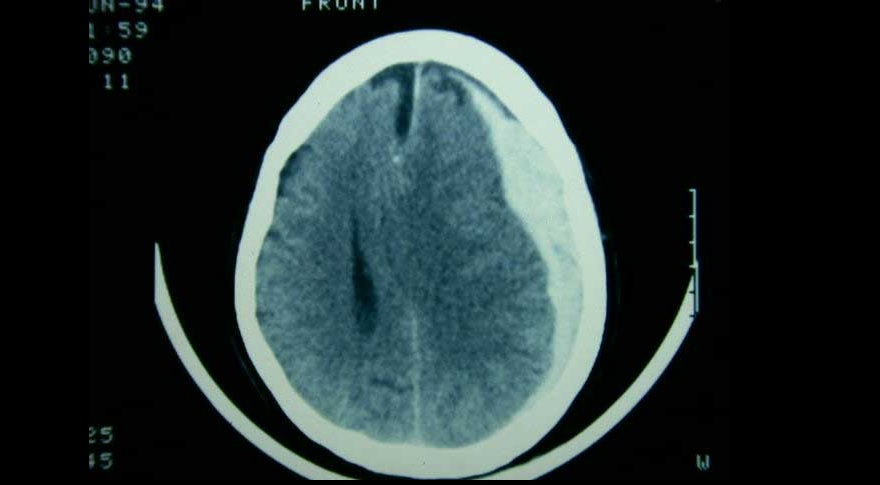

El tratamiento de pacientes con hematoma subdural agudo difiere según el centro de tratamiento, debido a la variación en el abordaje preferido. Una estrategia de tratamiento que prefirió un enfoque agresivo de evacuación quirúrgica aguda sobre el tratamiento conservador inicial no se asoció con un mejor resultado funcional. The Lancet Neurology, 5 de mayo de 2022.